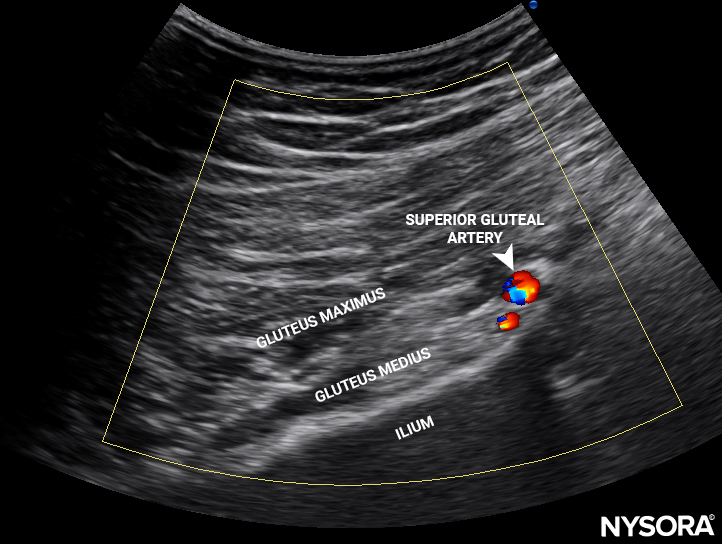

• Clear guidance on anatomical landmarks and sonoanatomy

• High-resolution clinical and ultrasound images

• Pelvis: Sacroiliac joint, piriformis muscle, and other injections for pelvic pain.